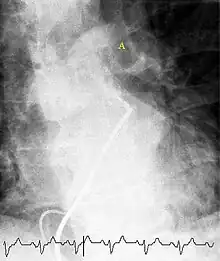

(A) After inhalation of 20 mCi of Xenon-133 gas, scintigraphic images were obtained in the posterior projection, showing uniform ventilation to lungs.

(B) After intravenous injection of 4 mCi of Technetium-99m-labeled albumin, scintigraphic images shown here in the posterior projection. This and other views showed decreased activity in multiple regions.

A ventilation/perfusion scan (or V/Q scan or lung scintigraphy) shows that some areas of the lung are being ventilated but not perfused with blood (due to obstruction by a clot).[17] This type of examination is as accurate as multislice CT, but is less used, due to the greater availability of CT technology. It is particularly useful in people who have an allergy to iodinated contrast, impaired kidney function, or are pregnant (due to its lower radiation exposure as compared to CT).[56][57][58] The test can be performed with planar two-dimensional imaging, or single photon emission tomography (SPECT) which enables three-dimensional imaging.[49] Hybrid devices combining SPECT and CT (SPECT/CT) further enable anatomic characterization of any abnormality.